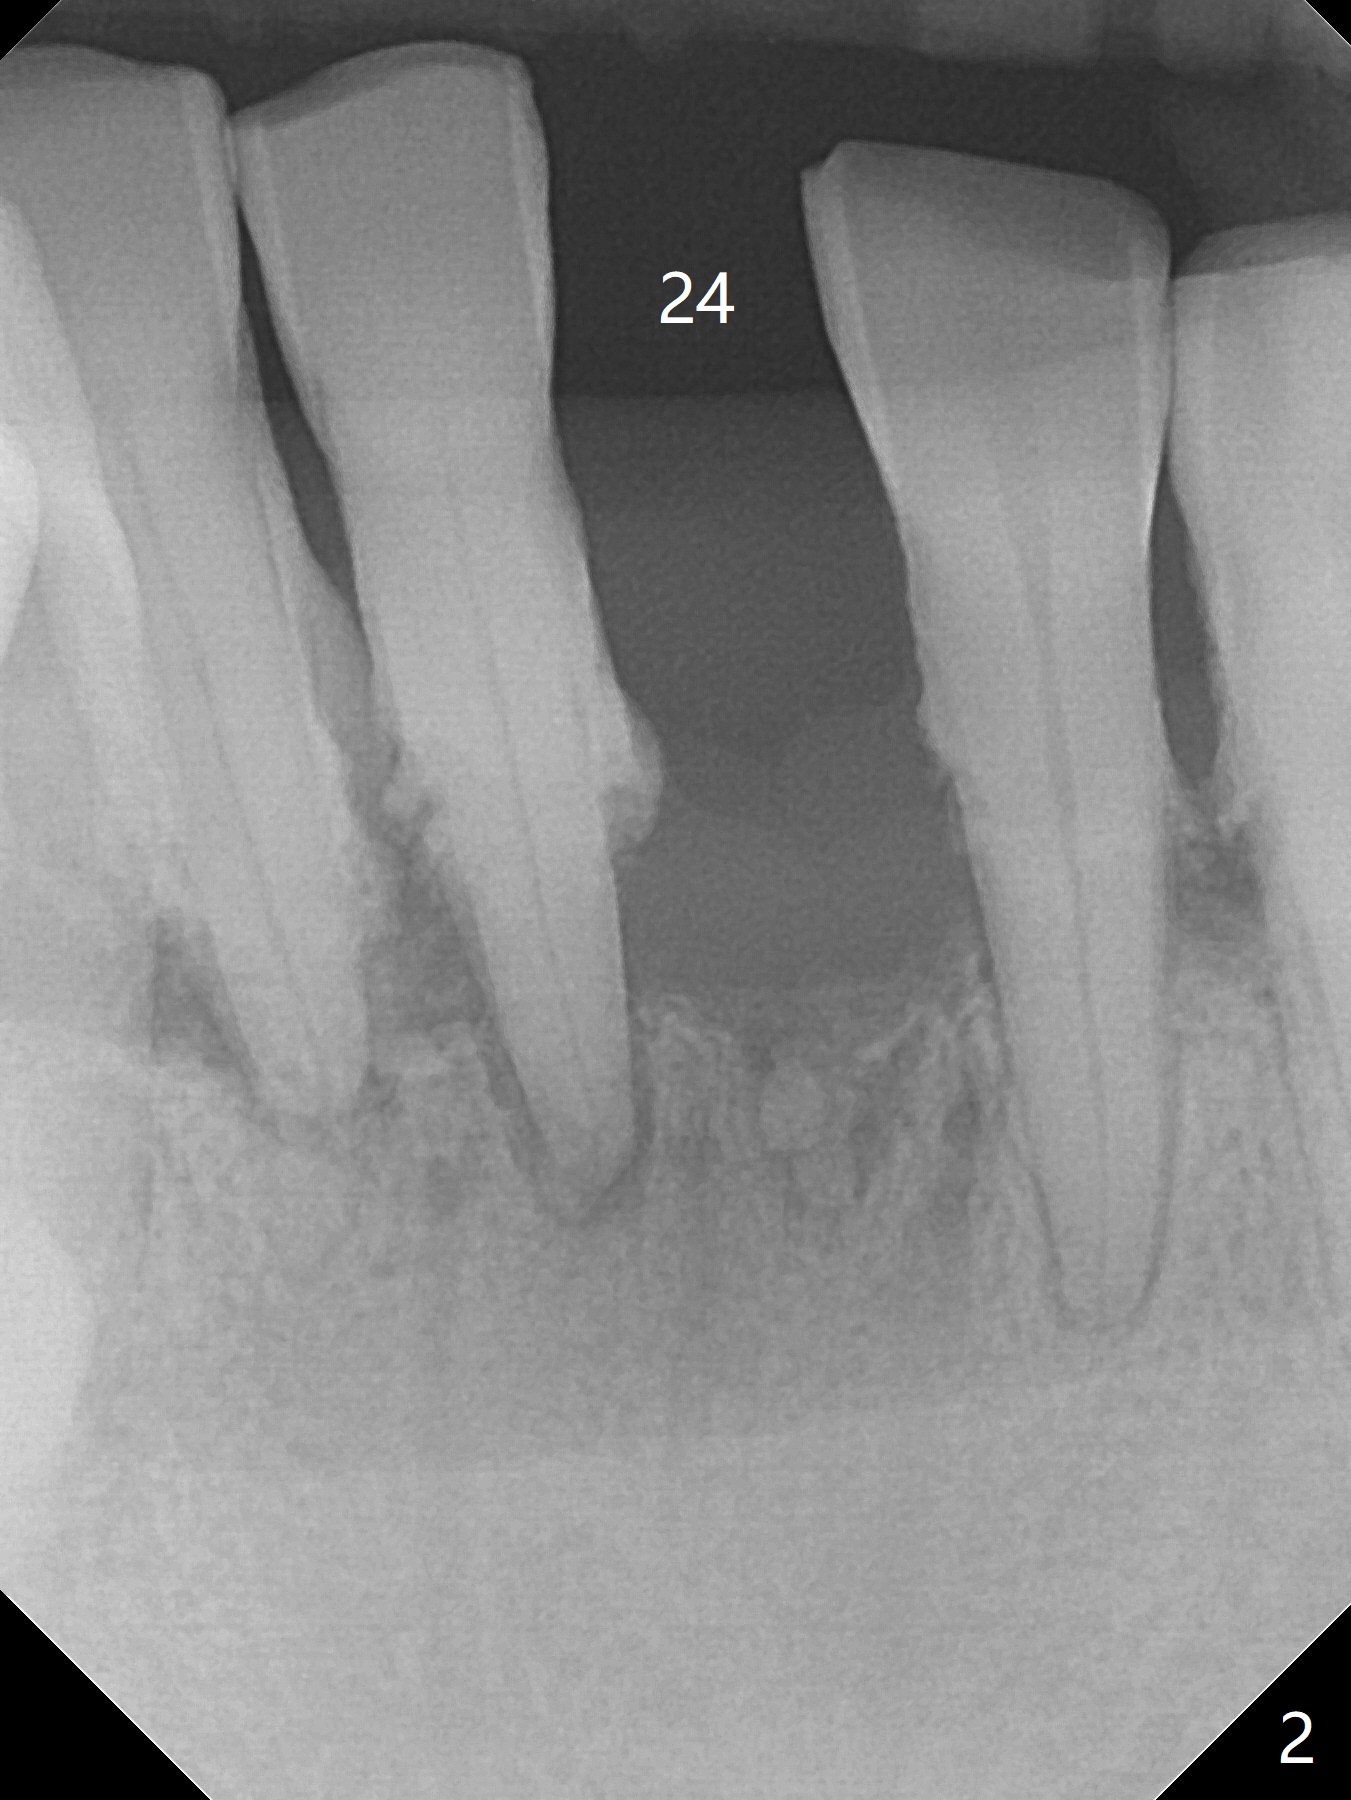

When the patient returns, the tooth #24 has exfoliated, while the ones at #25 and 26 has mobility III (Fig.1). The patient requests the tooth #23 extraction (Fig.2), but not #27. After SRP and extraction, osteotomy is initiated mesial to the sockets #23,25 and 26 (Fig.3,4) with intention to place 3 1-piece implants for 3 incisor crowns (Fig.5,6). Following Vanilla graft (Fig.5 *) a splinted provisional is fabricated to close the sockets (Fig.6). Peri-implant spaces close 5.5 months postop (Fig.7). Impression is taken after reprep for margin and parallelism (Fig.8). The final restoration consists of #23 single unit crown and #24-26 3-unit FPD (Fig.9). It appears that 2.5 mm 1-piece implants are not too small for the lower incisors (Fig.10-12), especially the central one (Fig.11). There may be perforation in the apical half of the lingual plate (L in Fig.10). The patient is not pleased with the shade of the #24-26 3-unit FPD (Fig.13 (6 months post cementation)). There is metal show through the abutments (*).